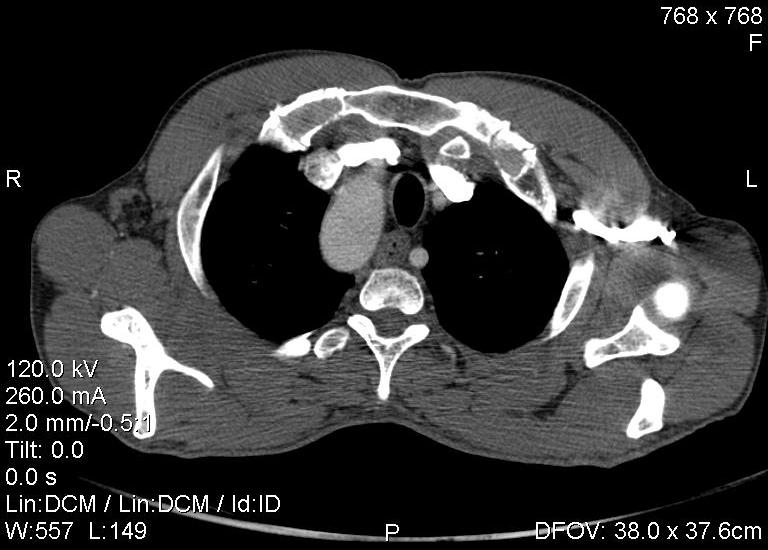

Пациент был направлен на КТ после рентгенографии ОГК, с направительным диагнозом: объёмное образование верхнего средостения.

это аномально расположенная грудная аорта

Конечно, дуга аорты идёт справа от позвоночника (декстра позиция); но есть и ещё одна аномалия той же группы: